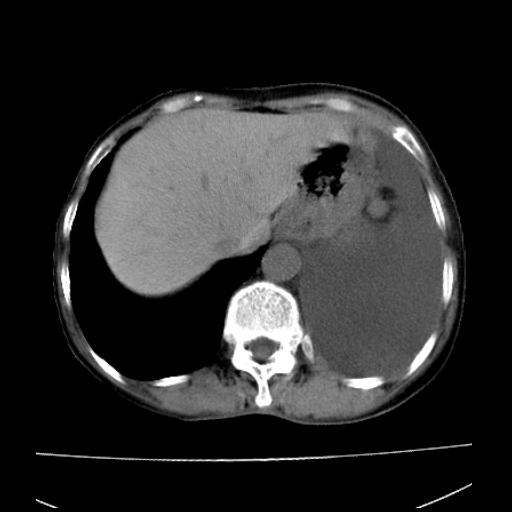

以下是引用随光逐影在2010-3-24 19:15:00的发言:[br]结合病史,考虑双肺及纵隔淋巴结多发转移、左侧胸膜转移并左侧大量胸水,左下肺膨胀不全。

以下是引用zxl51642在2010-3-24 18:49:00的发言:[br]结合乳腺癌术后病史,考虑双肺及纵隔淋巴结多发转移、左侧胸膜转移并左侧大量胸水、左下肺膨胀不全。